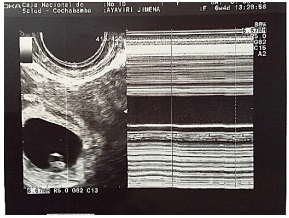

El ultrasonido transvaginal reveló útero en AVF de forma y contornos normales, dimensiones aumentadas de tamaño a expensas de saco gestacional ortotópico con embrión único vivo de 7 mm de LCC con actividad cardiaca ( Figura 1), correspondiente a seis semanas de gestación, una formación anexial ovoide de 31x19 mm en anexo derecho; Douglas con líquido libre escaso.